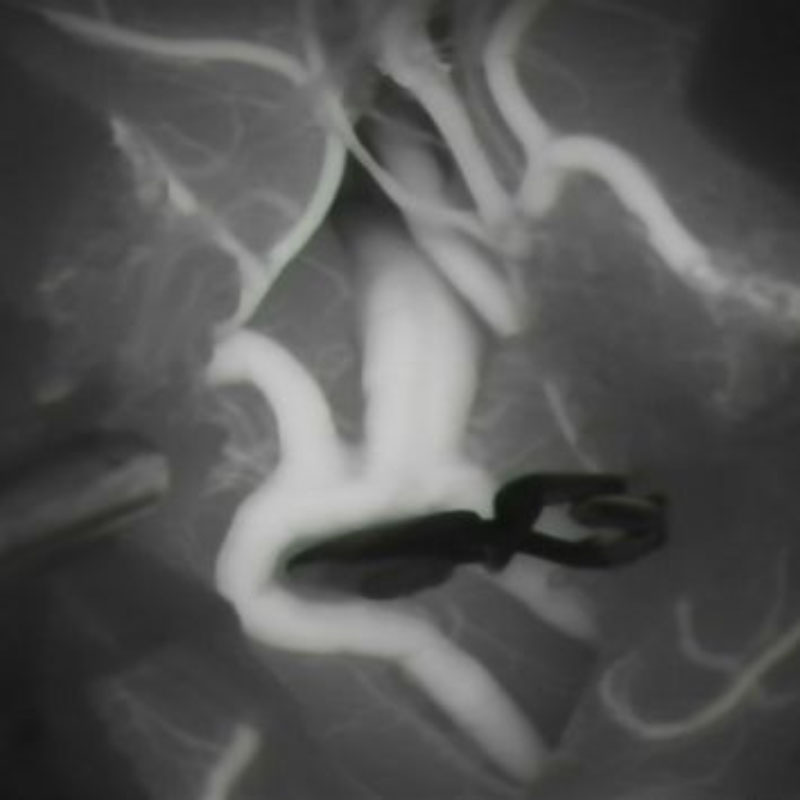

手術前

クリップ前

クリップ後

手術後

右中大脳動脈瘤

クリッピング術

術後血管撮影